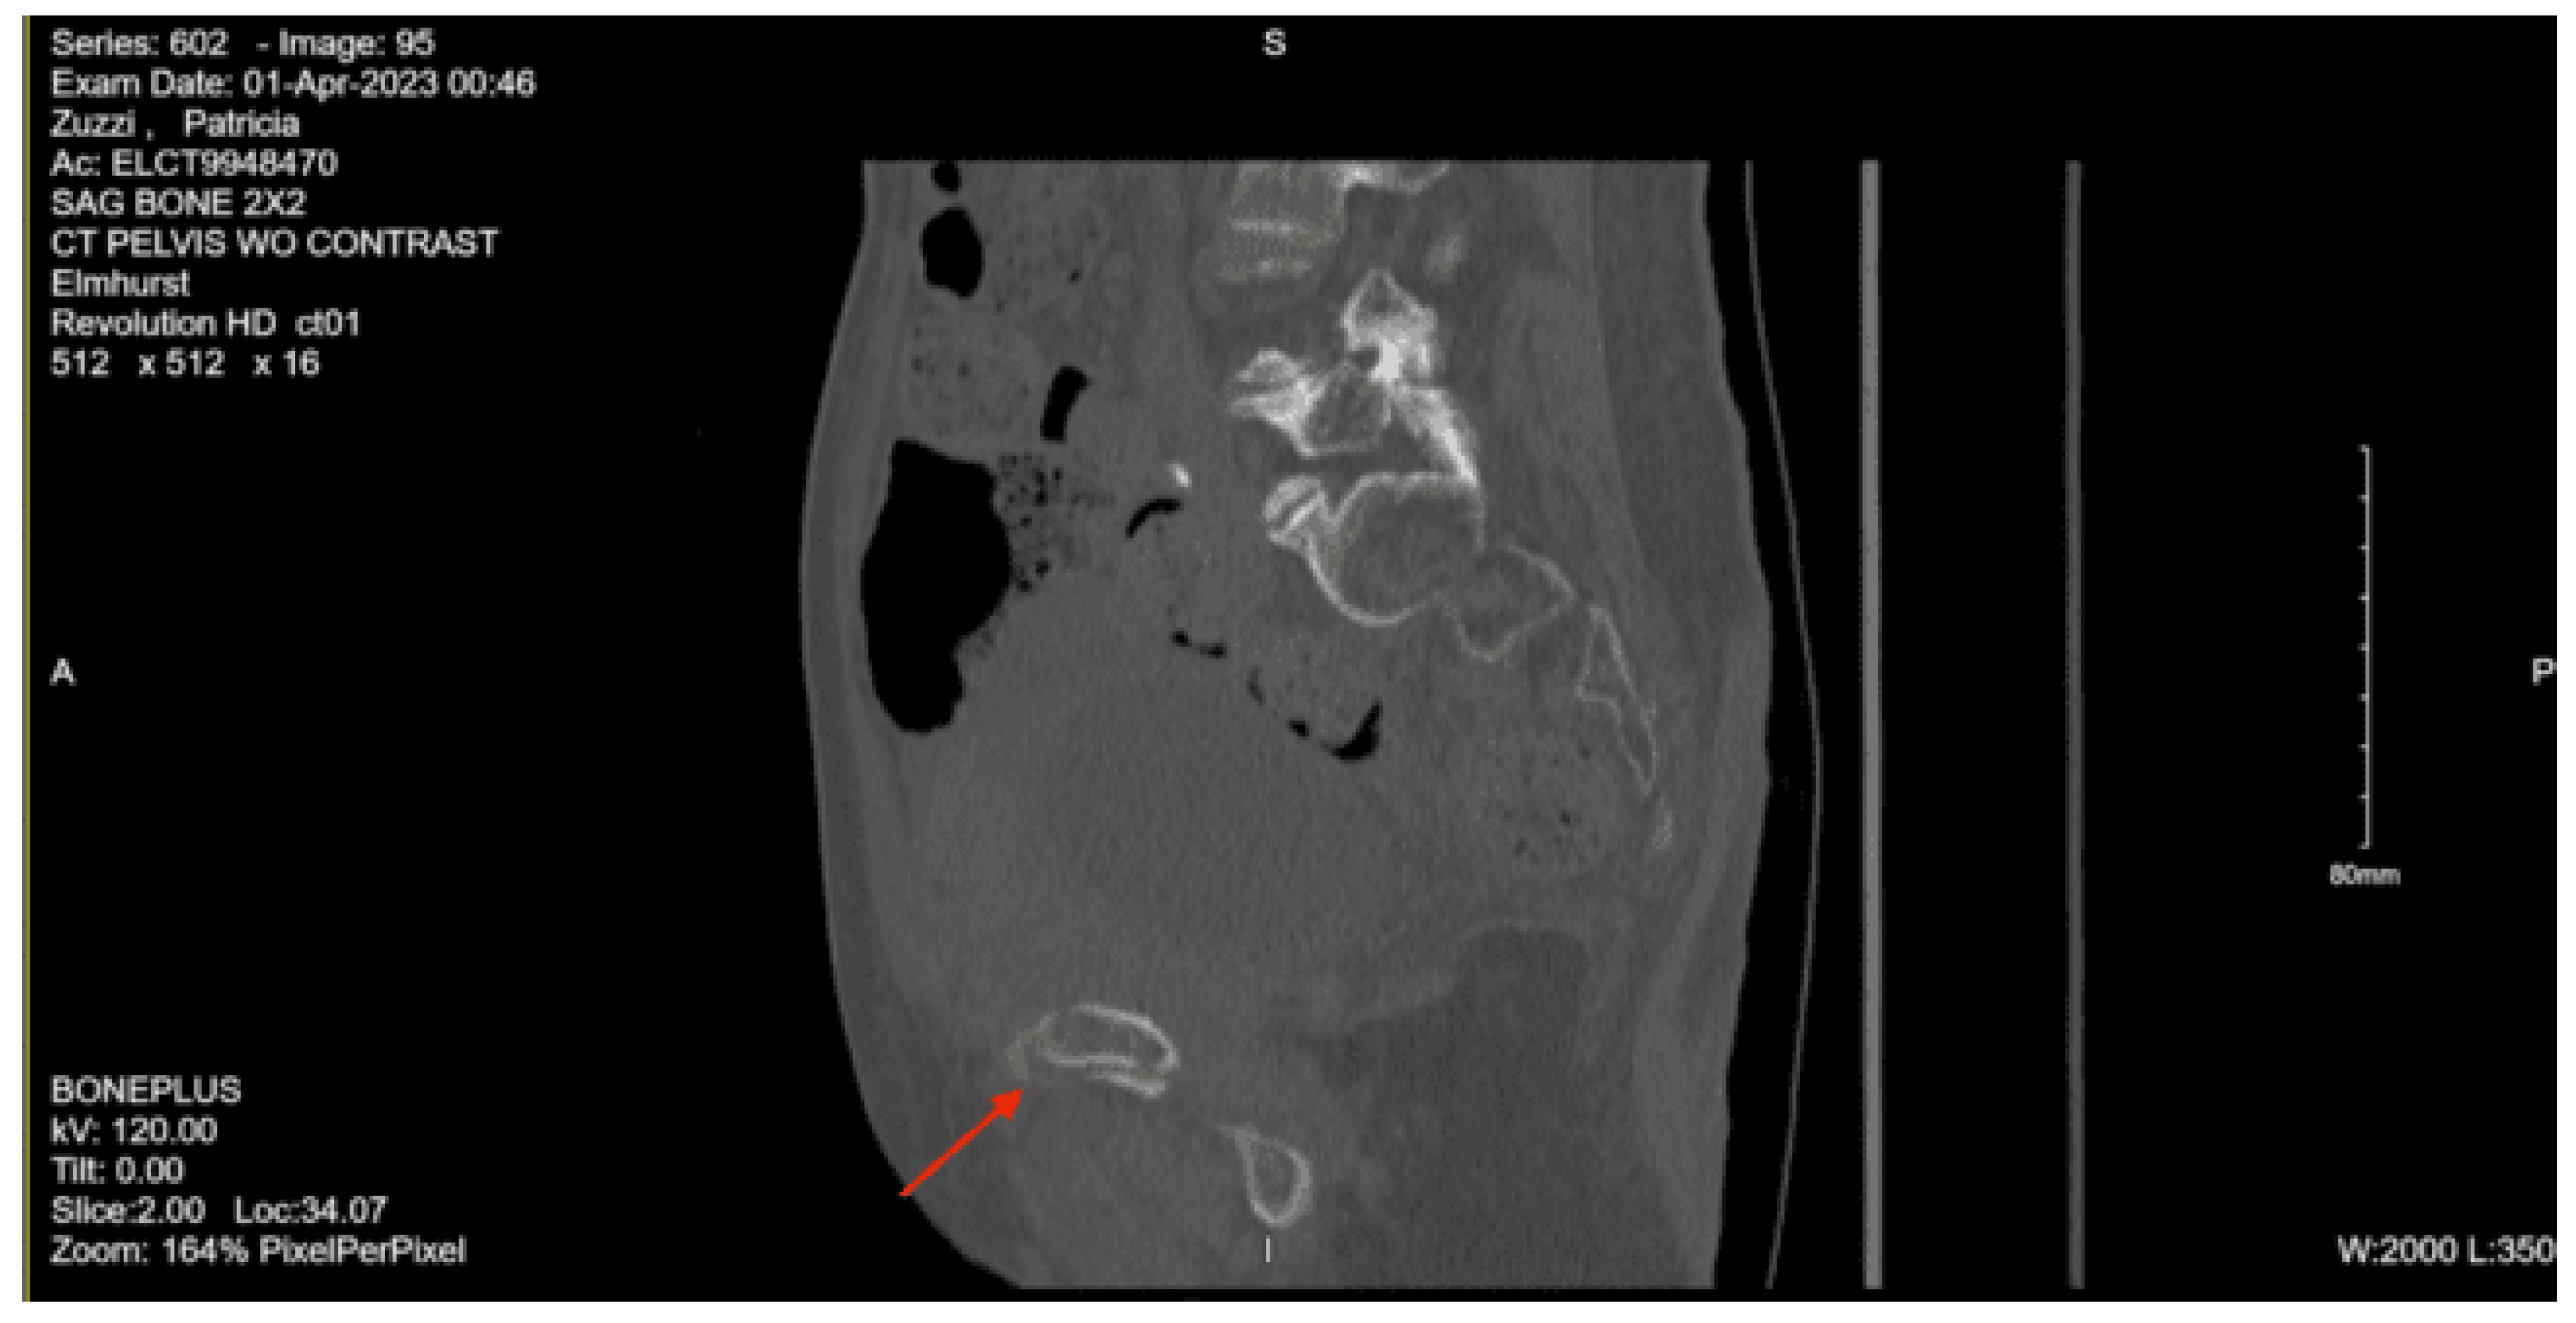

Imaging as shown in Figure 15 and Figure 16:

CT lumbar spine w/o contrast: Nondisplaced sacral fracture, approximately at the level of S4. Deformity at the sacrococcygeal junction, indeterminate chronicity. No other fractures identified. Diffuse osteopenia. Degenerative changes within the lower lumbar spine with grade 1 anterolisthesis of L4 over L5. No acute lumbar spine fractures identified

CT pelvis w/o contrast: Nondisplaced sacral fracture, approximately at the level of S4. Deformity at the sacrococcygeal junction, indeterminate chronicity. No other fractures identified. Diffuse osteopenia. Degenerative changes within the lower lumbar spine with grade 1 anterolisthesis of L4 over L5